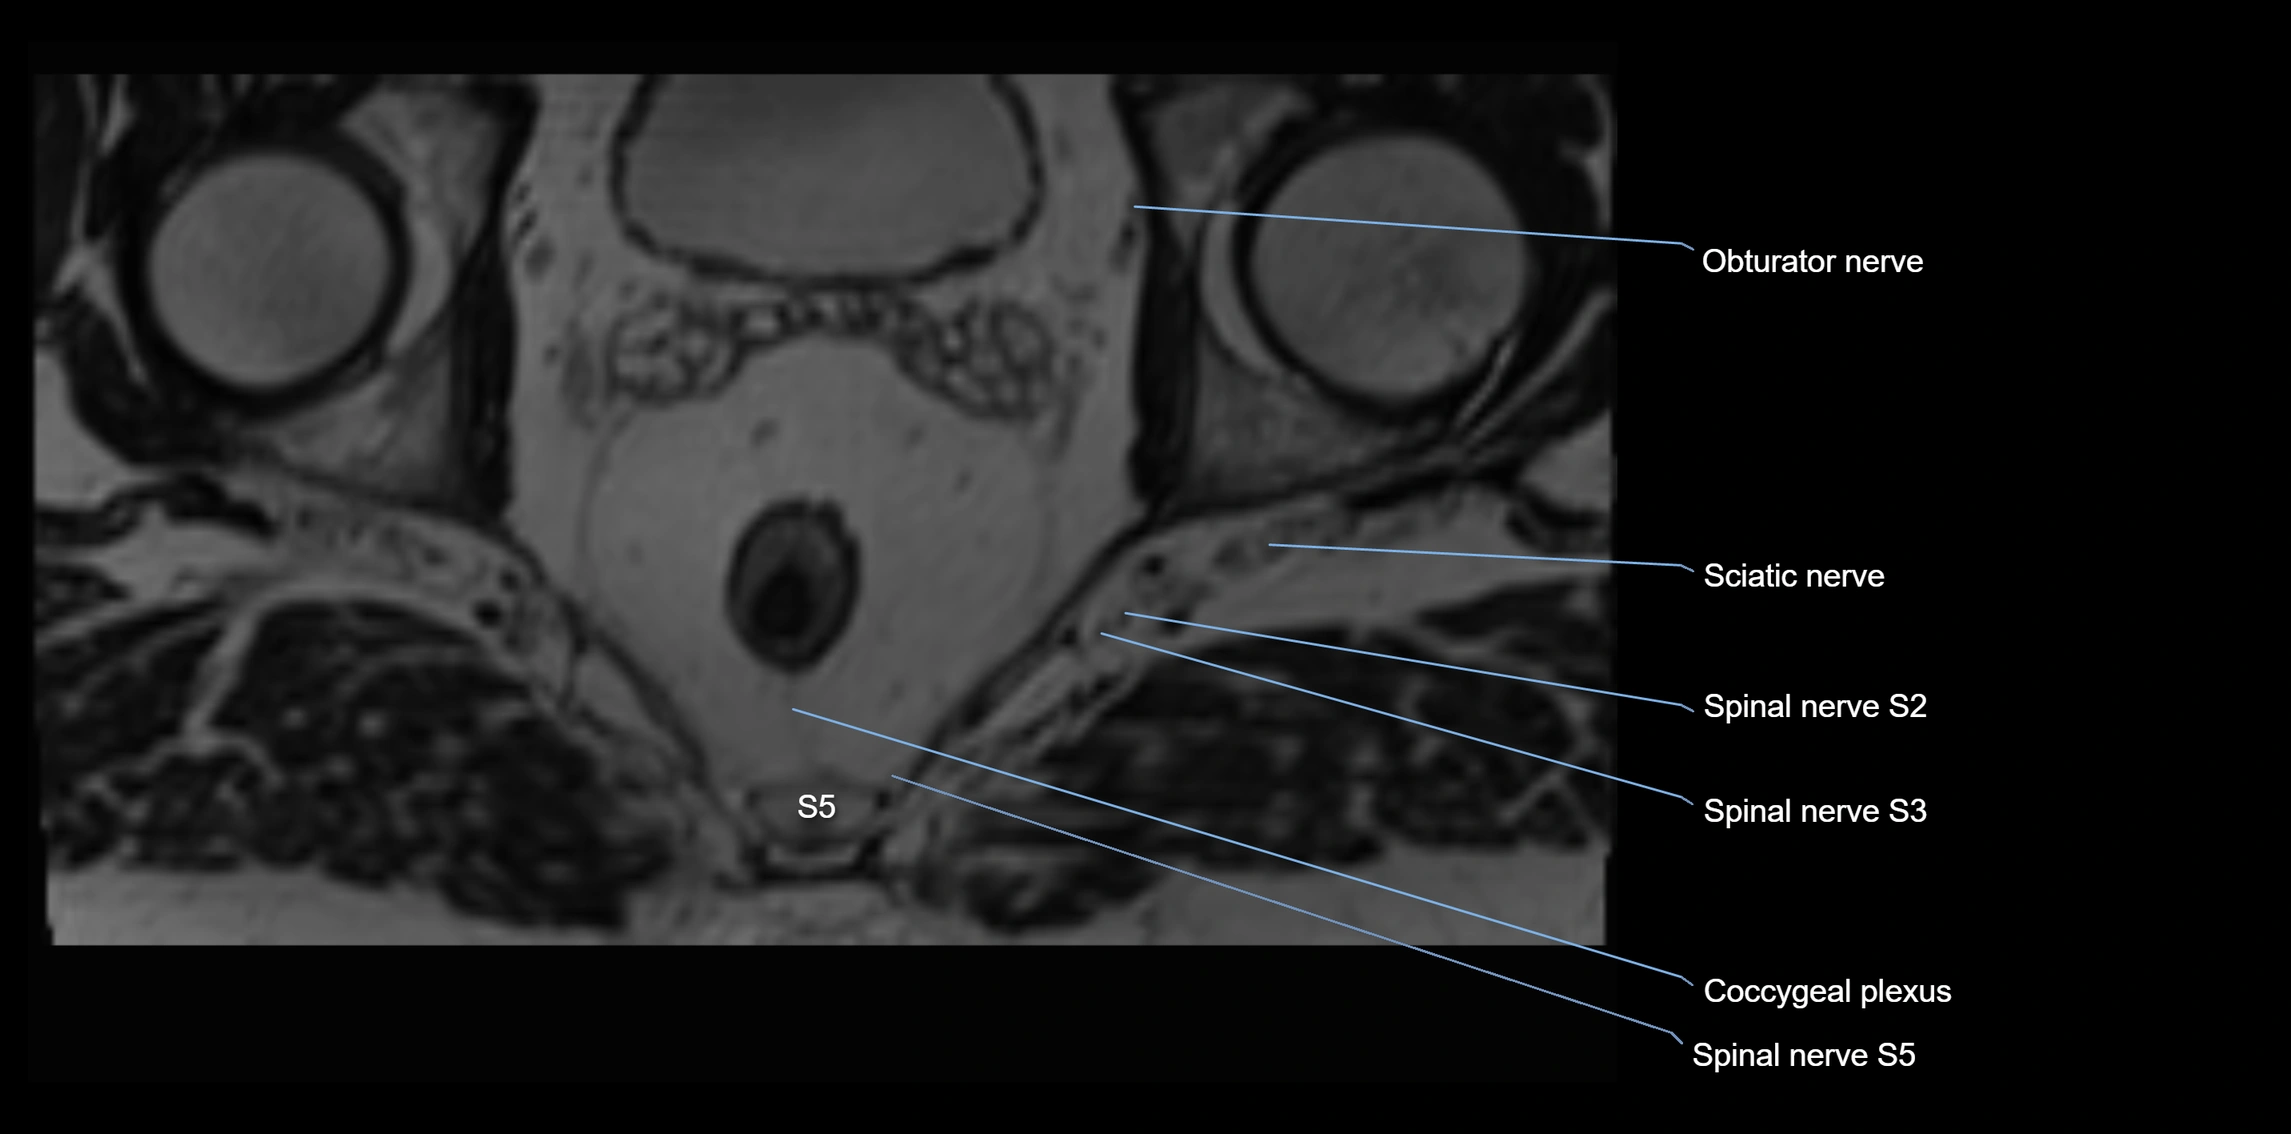

MRI Appearance

T1-weighted images:

• Nerve appears as a very thin low-to-intermediate signal intensity structure

• Surrounded by bright fat, aiding visualization

T2-weighted images:

• Nerve shows intermediate to mildly hyperintense signal compared to muscle

• Pathological involvement appears brighter

STIR (Short Tau Inversion Recovery):

• Normal nerve appears dark

• Inflamed or entrapped nerve appears bright hyperintense

T1 Fat-Sat Post-Contrast:

• Normal nerve enhances minimally

• Pathologic nerve (neuritis, entrapment, tumor infiltration) shows focal or diffuse enhancement

3D T2 SPACE / CISS:

• Nerve appears intermediate to mildly hyperintense compared to muscle

• Surrounded by bright fat or CSF, improving visualization

• Best sequence for mapping small pelvic nerves such as the anococcygeal